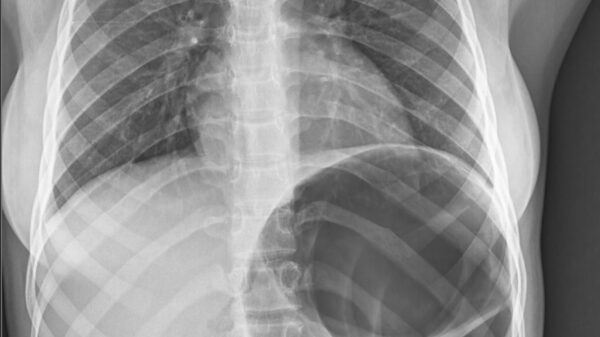

Cecal Volvulus

A teenage girl with vague abdominal symptoms was found to have cecal volvulus on imaging. Prompt recognition and surgical intervention led to a successful outcome.